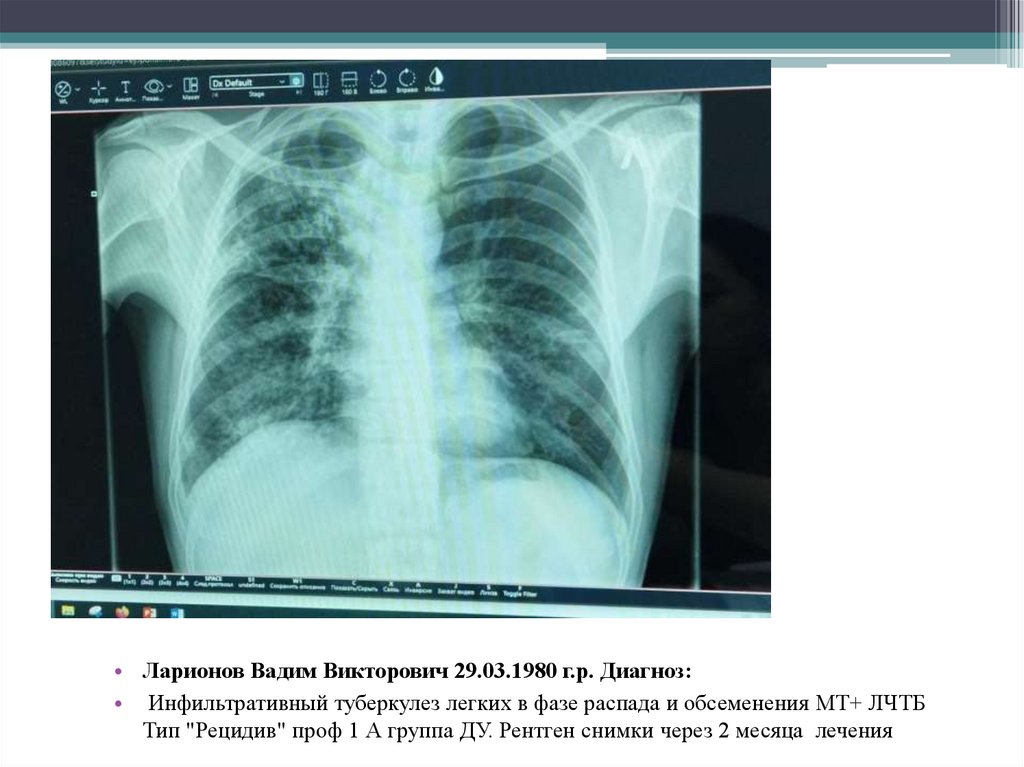

13. Ларионов Вадим Викторович 29.03.1980 г.р. Диагноз:  Инфильтративный туберкулез легких в фазе распада и обсеменения МТ+ ЛЧТБ Тип

• Ларионов Вадим Викторович

29.03.1980 г.р.

Диагноз:

Инфильтративный туберкулез легких в фазе

распада и обсеменения МТ+ ЛЧТБ Тип

"Рецидив" проф 1 А группа ДУ.

• Ларионов Вадим Викторович 29.03.1980 г.р. Диагноз:

• Инфильтративный туберкулез легких в фазе распада и обсеменения МТ+ ЛЧТБ Тип

"Рецидив" проф 1 А группа ДУ. Рентген снимки в начале лечения ЦВКК от 26.11.2024г

• Инфильтративный туберкулез легких в фазе распада и обсеменения МТ+ ЛЧТБ

Тип "Рецидив" проф 1 А группа ДУ. Рентген снимки через 2 месяца лечения